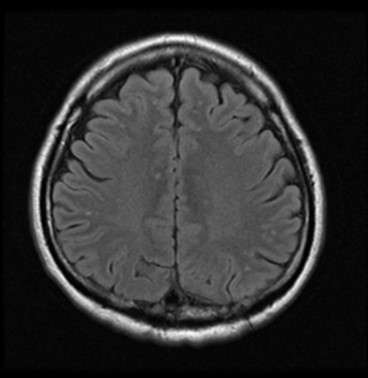

• 外科的にshunt遮断が行われた

• 術後脳実質の異常信号は消失